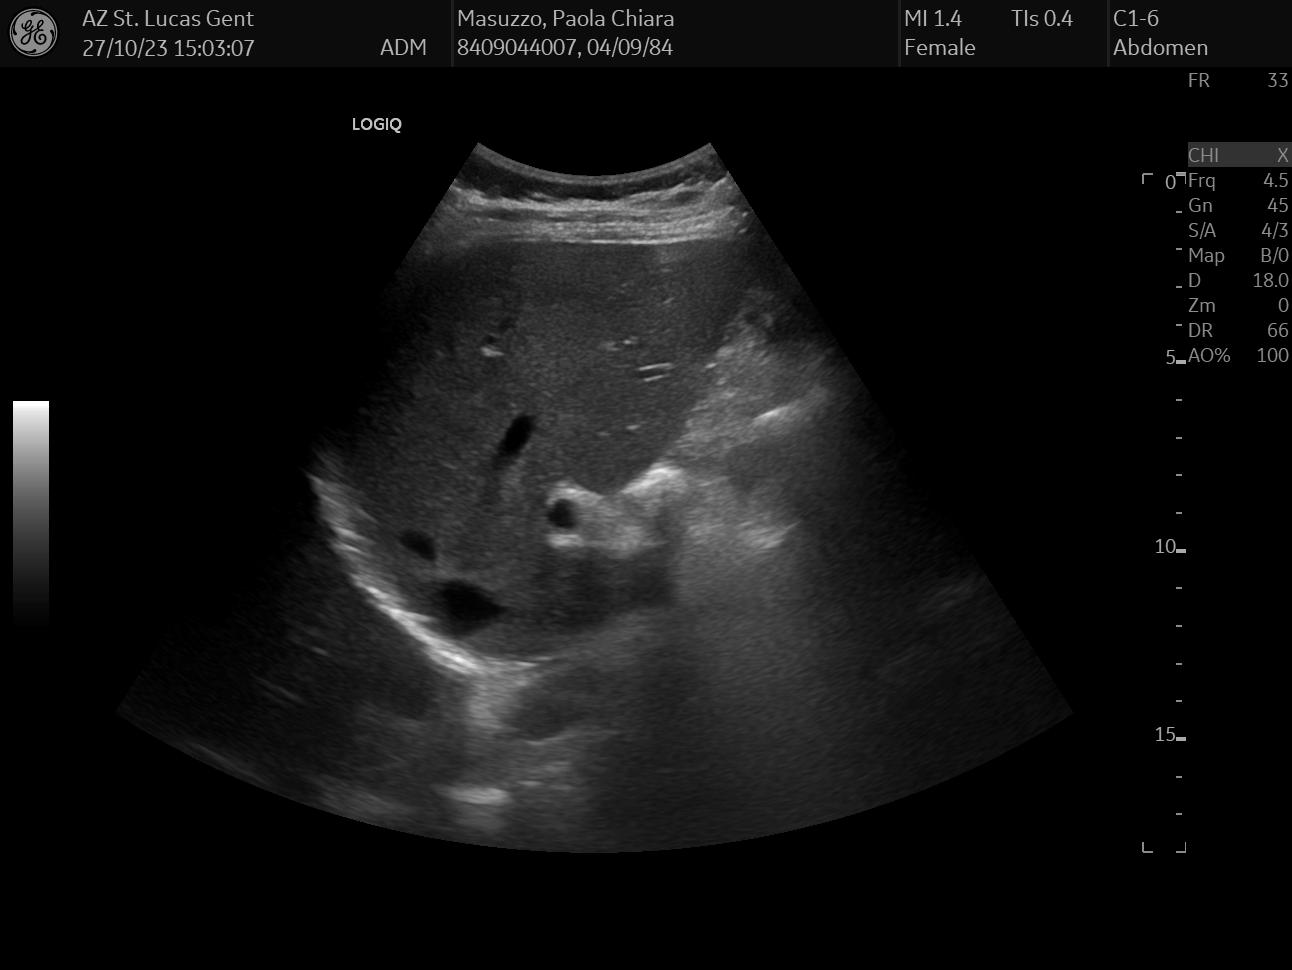

On the same day, I also had an abdomen ultrasound of my liver, gallbladder, and bile duct, which together can paint a pretty accurate status of your hepatic health - or lack thereof.

Like with any ultrasound exam carried over by a physician, the visit was pretty painless and I got the results on the spot: everything looked pretty normal. For this exam, I selected random data: I chose 3 images that looked the funniest to me, but I honestly have no idea what they mean.